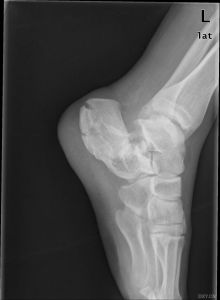

跟骨骨折影像病人有典型的外傷史,患足承重困難和足跟疼痛,局部觸痛、腫脹和皮下淤血斑亦多明顯。在較嚴重的壓縮骨折時,除可見到足後跟的高度變低和足跟橫徑變寬以及外踝下部正常凹陷消失外,距下關節話動亦完全喪失。但跟骨周邊骨折僅有局部腫脹及壓痛,而距下關節活動範圍多屬正常。x線正、側、軸位片可明確跟骨的結節關節角和其橫徑寬度的改變。

影像學表現

(1)跟骨前突骨折。

(2)跟骨結節的垂直骨折。

(3)載距突骨折。

(4)跟骨壓縮性骨折。

(5)跟骨粉碎性骨折。